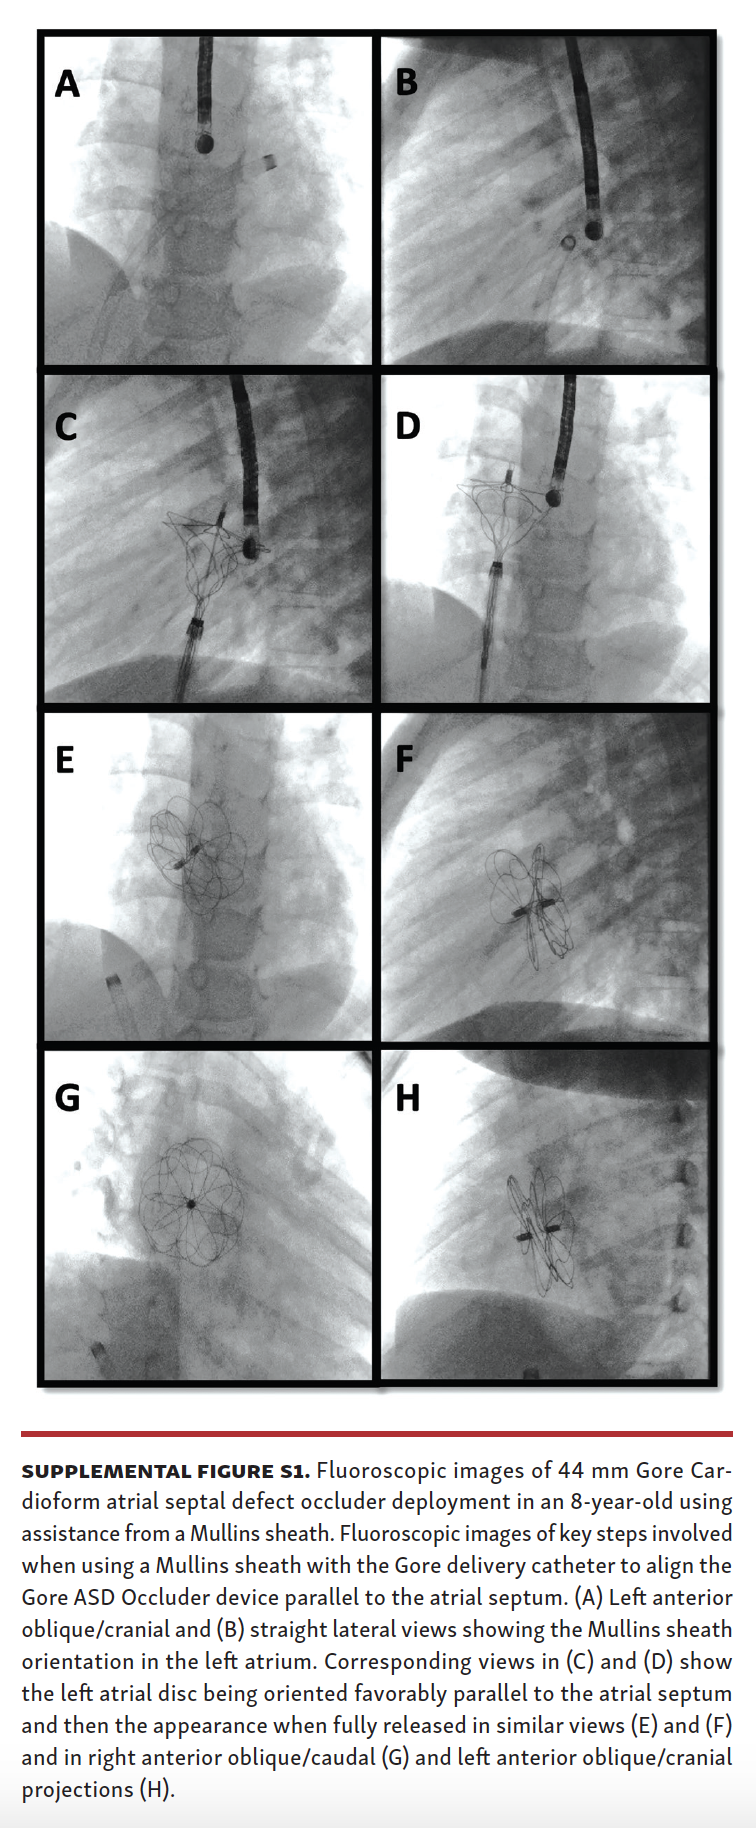

A total of 98 patients underwent attempted ASD closure during the study period (70 patients from the Gore ASSURED Clinical Study-Pivotal and Continued Access studies) and 28 patients after the study period. Of these patients, 52 underwent attempted secundum ASD closure using a long Mullins sheath (Supplemental Figures S1 and S2), while 46 patients underwent attempted secundum ASD closure with the Gore Cardioform delivery catheter through a short sheath in standard fashion.

Mullins-sheath facilitated Gore Cardioform ASD occluder delivery technique. The mechanism of favorable exaggeration of the angle of the Gore Cardioform ASD occluder delivery system when used with a Mullins sheath is seen in Figure 1. In large defects or in defects with deficient rims, the angulation of the Gore delivery catheter may not allow for alignment of the device parallel to the atrial septum, with resultant device prolapse superiorly through the defect into the right atrium (Figure 2). In such situations, the short sheath was exchanged for an appropriately sized 63 cm-long or 75 cm-long Mullins sheath in the left atrium and the dilator and wire were removed (same Fr size as required short sheath Fr size). When used in combination with a Mullins sheath, the angulation is exaggerated enough to facilitate better alignment parallel to the atrial septum (Figure 3). The Mullins sheath was rotated clockwise to assume a posterior orientation to align the device parallel to the atrial septum as it was being delivered. The Gore Cardioform ASD occluder delivery catheter was then advanced through the Mullins sheath, which was positioned with continuous clockwise rotation, often by the assistant, as the primary operator deployed the device. In some cases, despite this maneuver, the device was not aligned parallel to the atrial septum. In such cases, once the left atrial side of the device was deployed and aligned in the best possible way, the Mullins sheath was withdrawn (if 63 cm-long sheath was used) to the inferior vena cava or right atrium to serve as a “fixed point,” whereby further clockwise rotation of the Gore delivery catheter could be performed if needed to facilitate further device alignment as parallel to the atrial septum as possible (Figure 4). In some cases, the Gore delivery catheter was rotated 180° clockwise despite the use of the Mullins sheath to facilitate capture of the aortic and superior vena cava rims. Use of the Mullins sheath also facilitated delivery of the device when inferior disc prolapse into the left atrium was encountered (Figure 5). Finally, in some cases, the tip of the Gore Cardioform ASD occluder delivery catheter was also hand-shaped to further exaggerate its angle. The use of the Mullins sheath was at the discretion of the implanting physician.